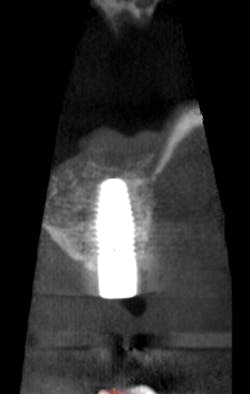

I prescribed a CBCT scan to evaluate site No. 14 prior to implant placement and to evaluate tooth No. 15. After capturing a CBCT scan on the CS 9300 (with a 5 cm x 5 cm field of view and a resolution of 90 μm), the image clearly showed a palatal root fracture on tooth No. 15 across from the cross-sectional and axial scan views (figs. 1, 2). Thanks to the enhanced diagnostic quality of the images, we decided to extract the tooth.

Figure 2: